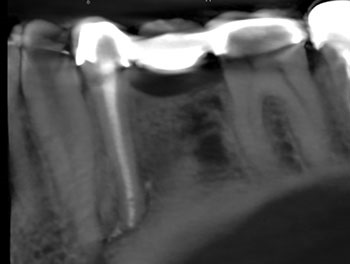

Case 12: Active irrigation

This patient presented for a second opinion after their dentist recommended extraction because of a VRF in the mesial root. The mesial root was surrounded by a U-shaped lesion, had a probing defect to the apex and all the canals were shaped with large flares. After discussing the possibility of VRF with the patient, re-treatment was recommended and accepted. No VRF was seen internally. Re-treatment was completed in a single visit, utilizing active irrigation and multisonic GentleWave technology. Complete healing occurred.

Endodontic Root Fracture Case Series

Fig.47: Preop PA.

Fig.48: Preop CBCT.

Fig.49: Postop PA.

Fig.50: Recall PA.

Fig.51: Recall CBCT.